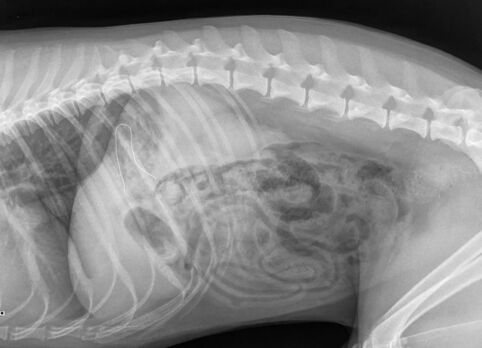

Luckily, his owner recognised the risk of this causing damage to his gastro-intestinal tract, and brought him straight to our Out of Hours Emergency Service. An x-ray was taken to check if the mask contained a nose wire, as this increases the risk of complications – it did, but since this appeared small and flexible our team opted to make Kobe vomit in the hope of retrieving the mask.